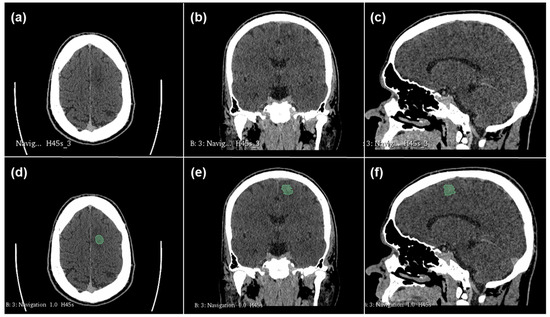

2.1. Radiomics